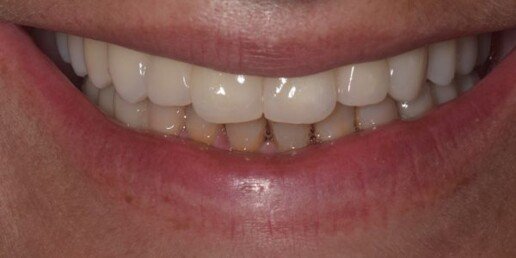

Caso 4

Riabilitazione totale superiore e inferiore su impianti. Gli esiti di una paradontite grave portano alla perdita totale dei denti. E’ necessario ricostruire sia i denti sia i tessuti molli e anche l’osso per il sostegno delle labbra.

Prima

Dopo